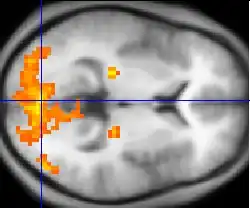

Vyšetření zobrazovacími metodami

Vyšetření zobrazovacími metodami slouží především k posouzení struktury. Klasický rentgenový snímek může poskytnout cenné informace o změnách na lebce a páteři. Počítačovou tomografií lze zobrazit i vlastní tkáň mozku, mozkové komory, krvácení a expanzivní procesy. Někdy je vhodné vyšetření nukleární magnetická rezonance, například při vyšetřování rozsahu postižení roztroušenou sklerózou. Zejména pro vyšetření tepen zásobujících mozek krví se používá ultrasonografie a angiografie. V některých případech je třeba monitorovat funkční aktivitu jednotlivých regionů mozkové kůry; k tomu se hodí pozitronová emisní tomografie.